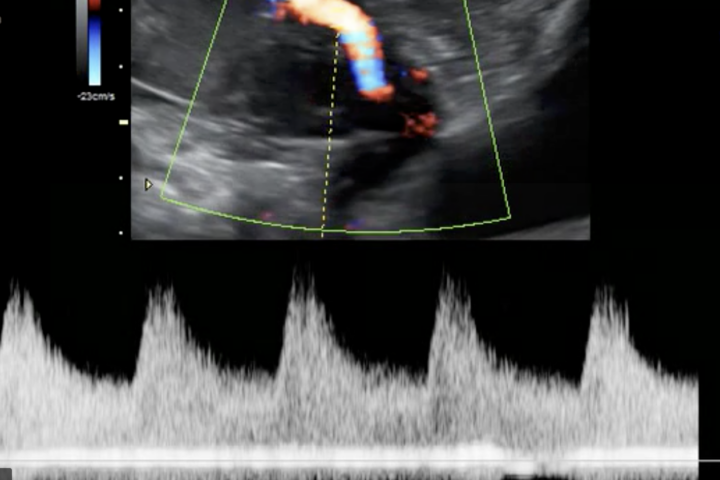

Le ecografie in gravidanza vengono fatte per monitorare lo stato di salute del bambino.  Non emettono radiazioni ma mandano onde ad altra frequenza attraverso la sonda ecografica. Le onde rimbalzano contro i tessuti solidi e vengono convertite in immagini, quelle che poi vediamo nel monitor dell'ecografista.

L'ecografia è un importante strumento diagnostico che permette di fornire immagini bidimensionali dell'anatomia fetale. Si chiama ecografia perché utilizza le onde sonore ad alta frequenza per produrre immagini degli organi interni e del bambino che portiamo in grembo.